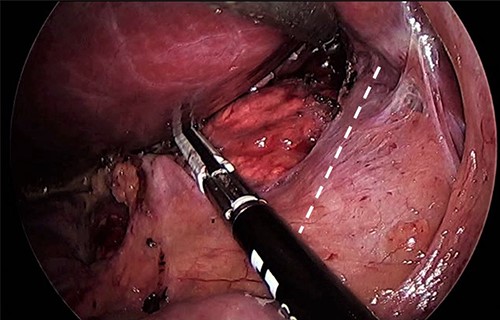

As for the LRA, ports are inserted in similar fashion as the LLA but with more to the right side. An additional port at the right midclavicular line is an optional (Fig. 5). In Patient 1, we started with the LLA to control the blood pressure caused by the adrenal gland and to prevent unnecessary bleeding from occurring. Conversely, we started with LSG in Patient 2 because the priority was controlling his comorbidities by weight reduction. The right hepatic lobe was retracted to expose the subhepatic area. The right hepatic ligaments were released, exposing the inferior vena cava. Dissection lateral to the IVC was continued exposing the right adrenal (Fig. 6). Complete dissection of the adrenal gland was completed and the pedicle was controlled using energy device (Fig. 7). There was constant communication with the anesthesia team during the surgery. After complete dissection of the adrenal gland, it was placed in the endobag and the LSG was conducted similar to the above-mentioned steps (Fig. 8).

Port placement in Patient 2. The port marked with white star is an additional/optional port for better assistance in LRA.